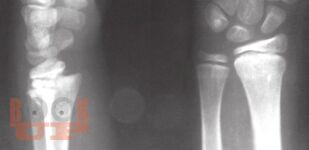

В настоящих методических рекомендациях обобщены научные данные и личный профессиональный опыт организации рентгеновской службы, описаны методы лучевой диагностики. Освещаются методы исследования органов и систем человека с нормальной анатомией, эмбриогенезом, рентгеноанатомией, а также рентгеносемиотика различных патологических состояний у взрослых и детей.